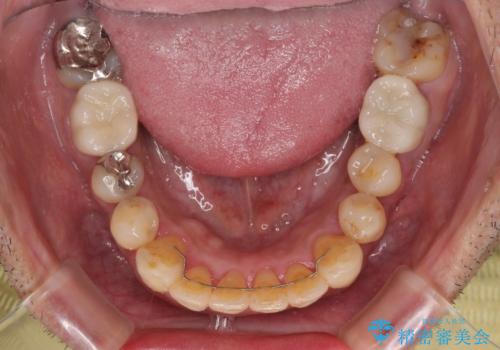

隠れている前歯 インビザライン矯正治療と前歯のセラミック治療

- 隠れるほどに内側に転位しいてる前歯を気にして来院された患者様です。

仕事柄海外出張が多いとのことで、インビザラインにて矯正治療を行うこととしました。

矯正治療後は、前歯や下顎の奥歯など、むし歯治療途中の歯をオールセラミッククラウンにて補綴治療を行うこととしました。

内側に転位していた前歯は、矯正治療では治しきることができませんでしたが、幸いにもオールセラミッククラウンに置き換える予定であったため、希望通りの仕上がりとなりました。